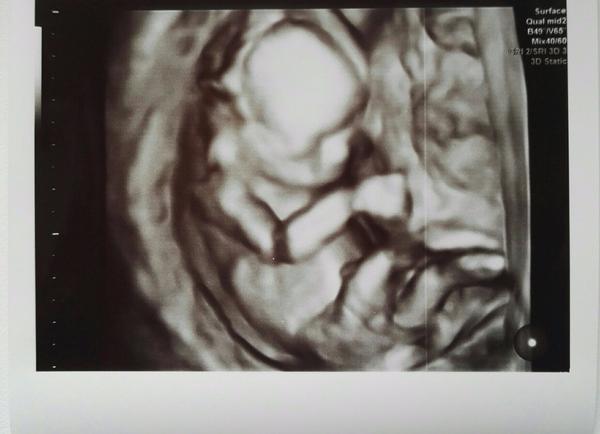

Pripajam foto maleho zazraku ❤

Baby, vsetkym vam uprimne zelam, nech sa zadari a dockate sa vytuzenehi bruska 🤰